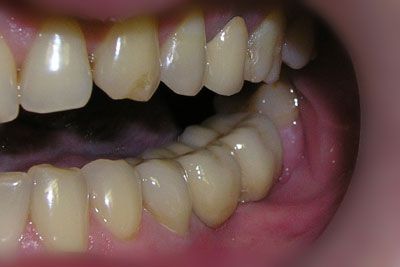

Через четыре месяца было выполнено протезирование, изготовлено две коронки на имплантаты и одиночная коронка на 35 зуб. Функция жевания восстановлена полностью.

Эту работу выполнили: хирург-имплантолог Кики Ф.Р., зубной техник Крапухин Н.Н. и стоматолог-ортопед, зав.отд.стоматологии Васин Ю.А.